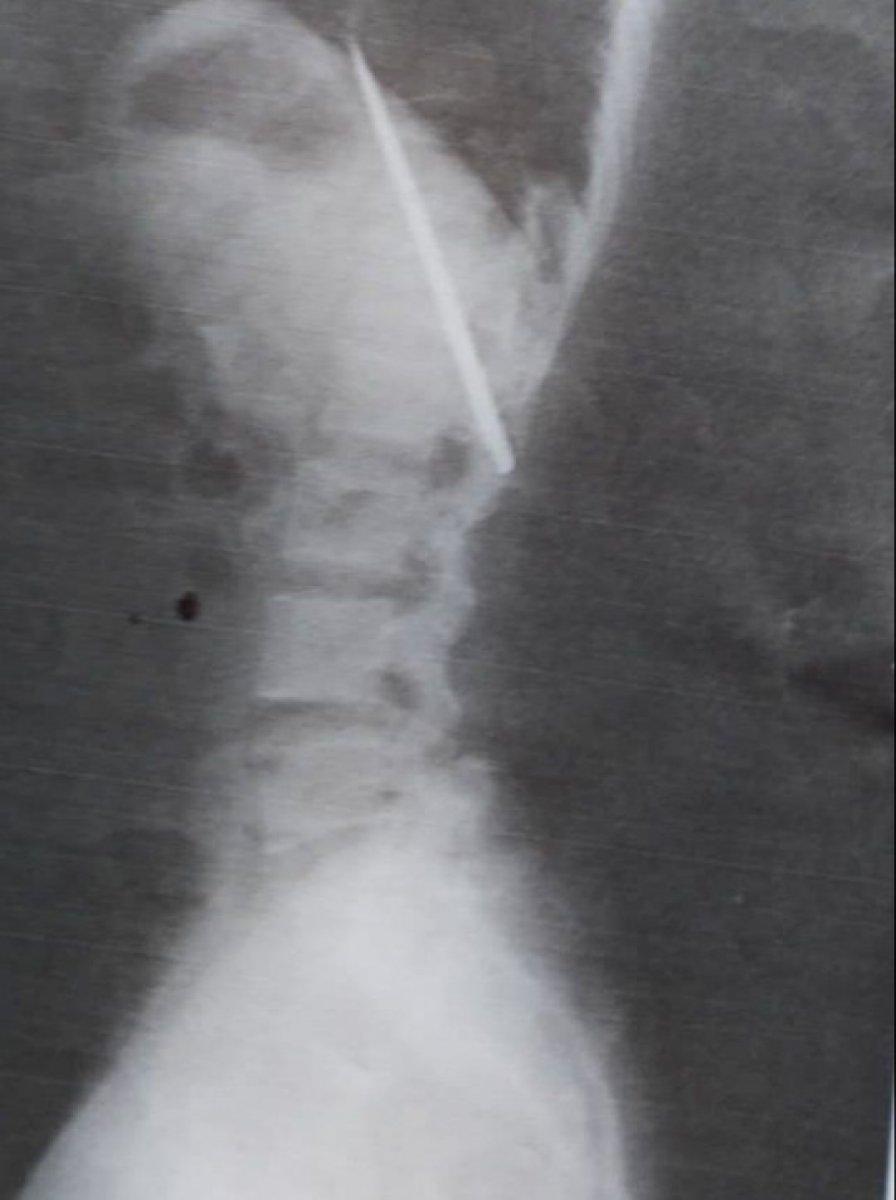

RÖNTGEN ÇEKİLMEDEN YARAYA MÜDAHALE EDİLDİ

Tomao hastaneye kaldırılırken, buradaki doktor önce röntgen çekmek yerine doğrudan yaraya müdahalede bulundu.

Filipinli genç ile ilgili gerçek, iş başvurusu sırasında talep edilen röntgen belgesinde ortaya çıktı.

25 yaşındaki Tomao, 15 ay önce yaşadığı olayda bıçağın akciğerlerine yakın bir yerde saplandığını öğrenince şaşkına döndü.